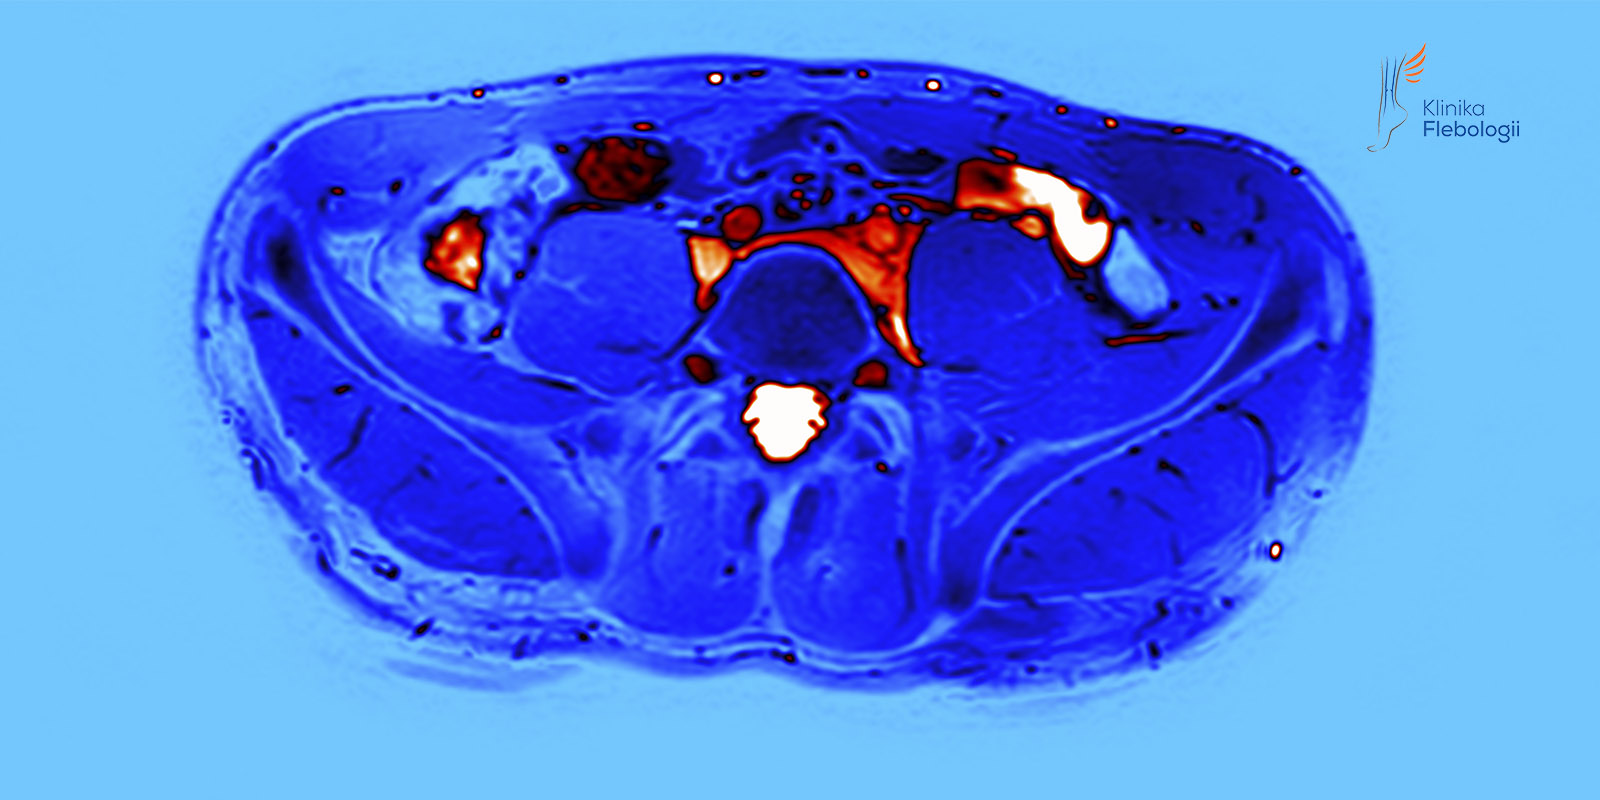

Współczesne badania obrazowe, w tym wykorzystywane na co dzień w Klinice Flebologii badania USG Doppler żył miednicy i jamy brzusznej oraz wenografia rezonansu magnetycznego (MRV), sugerują, że również u panów znaczna część przypadków niewydolności żylnej kończyn dolnych ma charakter wtórny.

Z praktyki zespołu Kliniki Flebologii wynika, iż duże żylaki (śr. > 5 mm) zlokalizowane w worku mosznowym często wynikają z przyczyn, które w rutynowej diagnostyce urologicznej są zwykle pomijane. Z tego względu w diagnostyce rozszerzonej zalecane jest wykonanie badań USG Doppler żył miednicy i jamy brzusznej oraz wenografii metodą rezonansu magnetycznego.

Leczenie żylaków powrózka nasiennego przez lekarzy Kliniki Flebologii poprzedzone jest zawsze wnikliwą diagnsotyką obrazową (USG Doppler żył miednicy i jamy brzusznej, wenografią MR lub TK oraz flebografią wykonywaną śródzabiegowo).